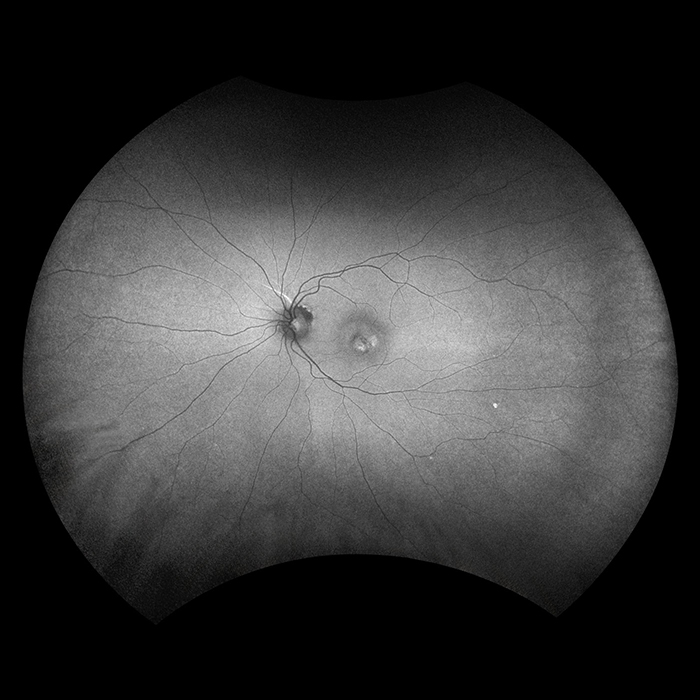

MonacoPro

MonacoPro takes the proven Optos technology further by integrating cutting-edge MonacoPro SD-OCT image quality into every exam. Engineered for efficiency, MonacoPro captures up to five imaging modalities for both eyes in just 90 seconds, optimizing workflow, streamlining diagnostics, and delivering superior patient care.

Why MonacoPro?

The MonacoPro captures up to five imaging modalities for both eyes in just 90 seconds, optimizing workflow, streamlining diagnostics, and delivering superior patient care.

MonacoPro imaging modalities and image viewing options:

optomap Image Modalities

- color rg

- Sensory Retina

- Choroidal

- green af

- SD-OCT